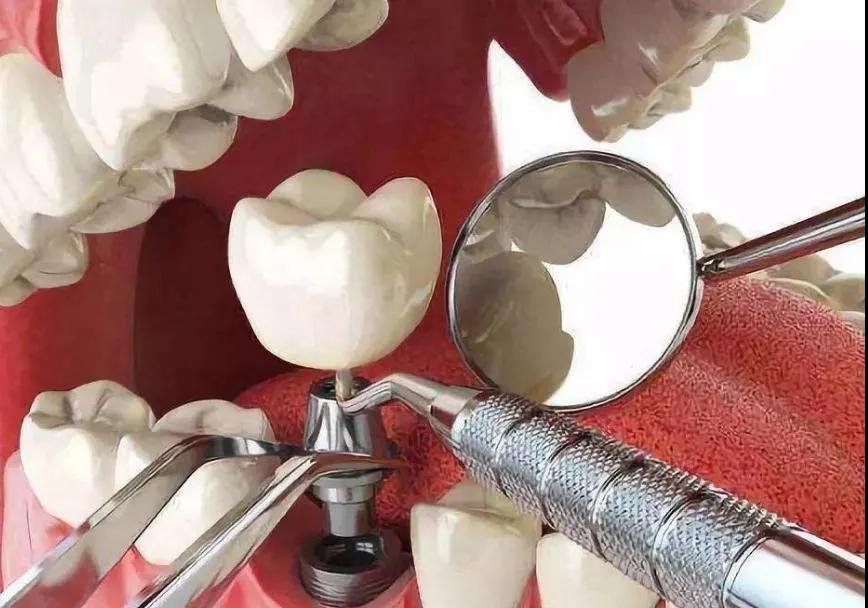

种植牙:拍全景片可以确定牙槽骨的质量的评价及种植体大小、长短,也可以检查一下牙周状况,牙周状况不好,需要稳定牙周状况,然后才可以进行种植牙手术。